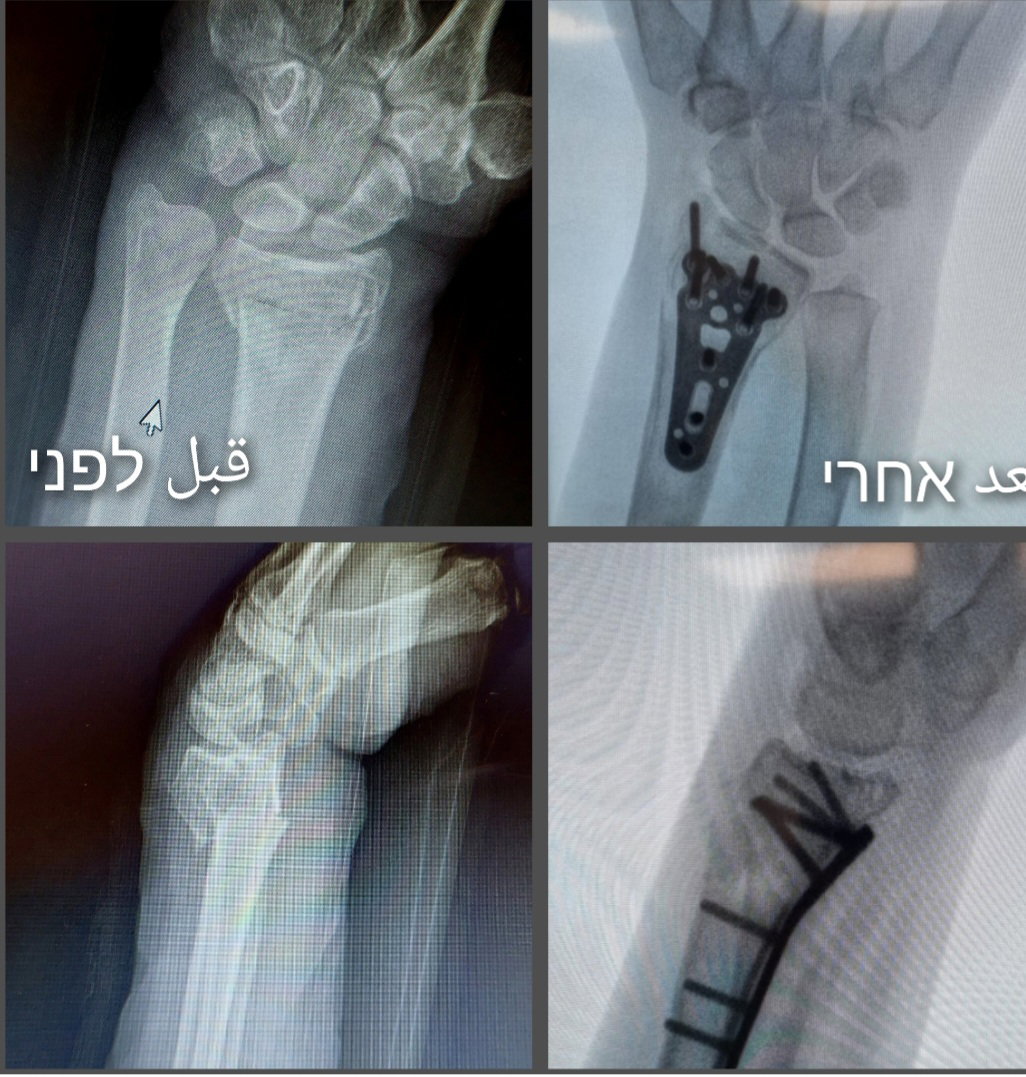

הניתוח השכיח ביותר לשברי רדיוס דיסטלי הוא שיחזור פתוח של חלקי השבר ע"י פתיחה והגעה לשבר, לאחר מכן קיבוע של השבר עם פלטה מטיטניום וברגים העוברים דרך הפלטה על מנת שחלקי השבר לא יזוזו עוד ויתחברו בעמדה טובה. הניתוח מתבצע בהרדמה